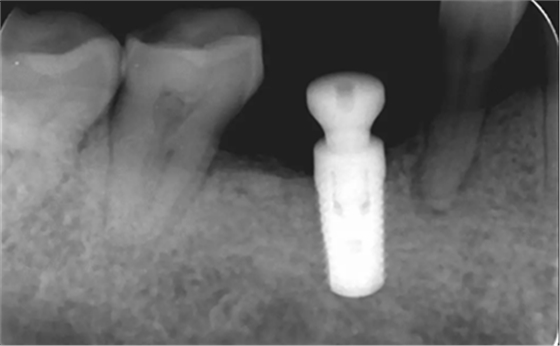

植骨术后半年根尖片,种植体周围愈合较好远中少量骨吸收。

(摄于2018年4月20日)